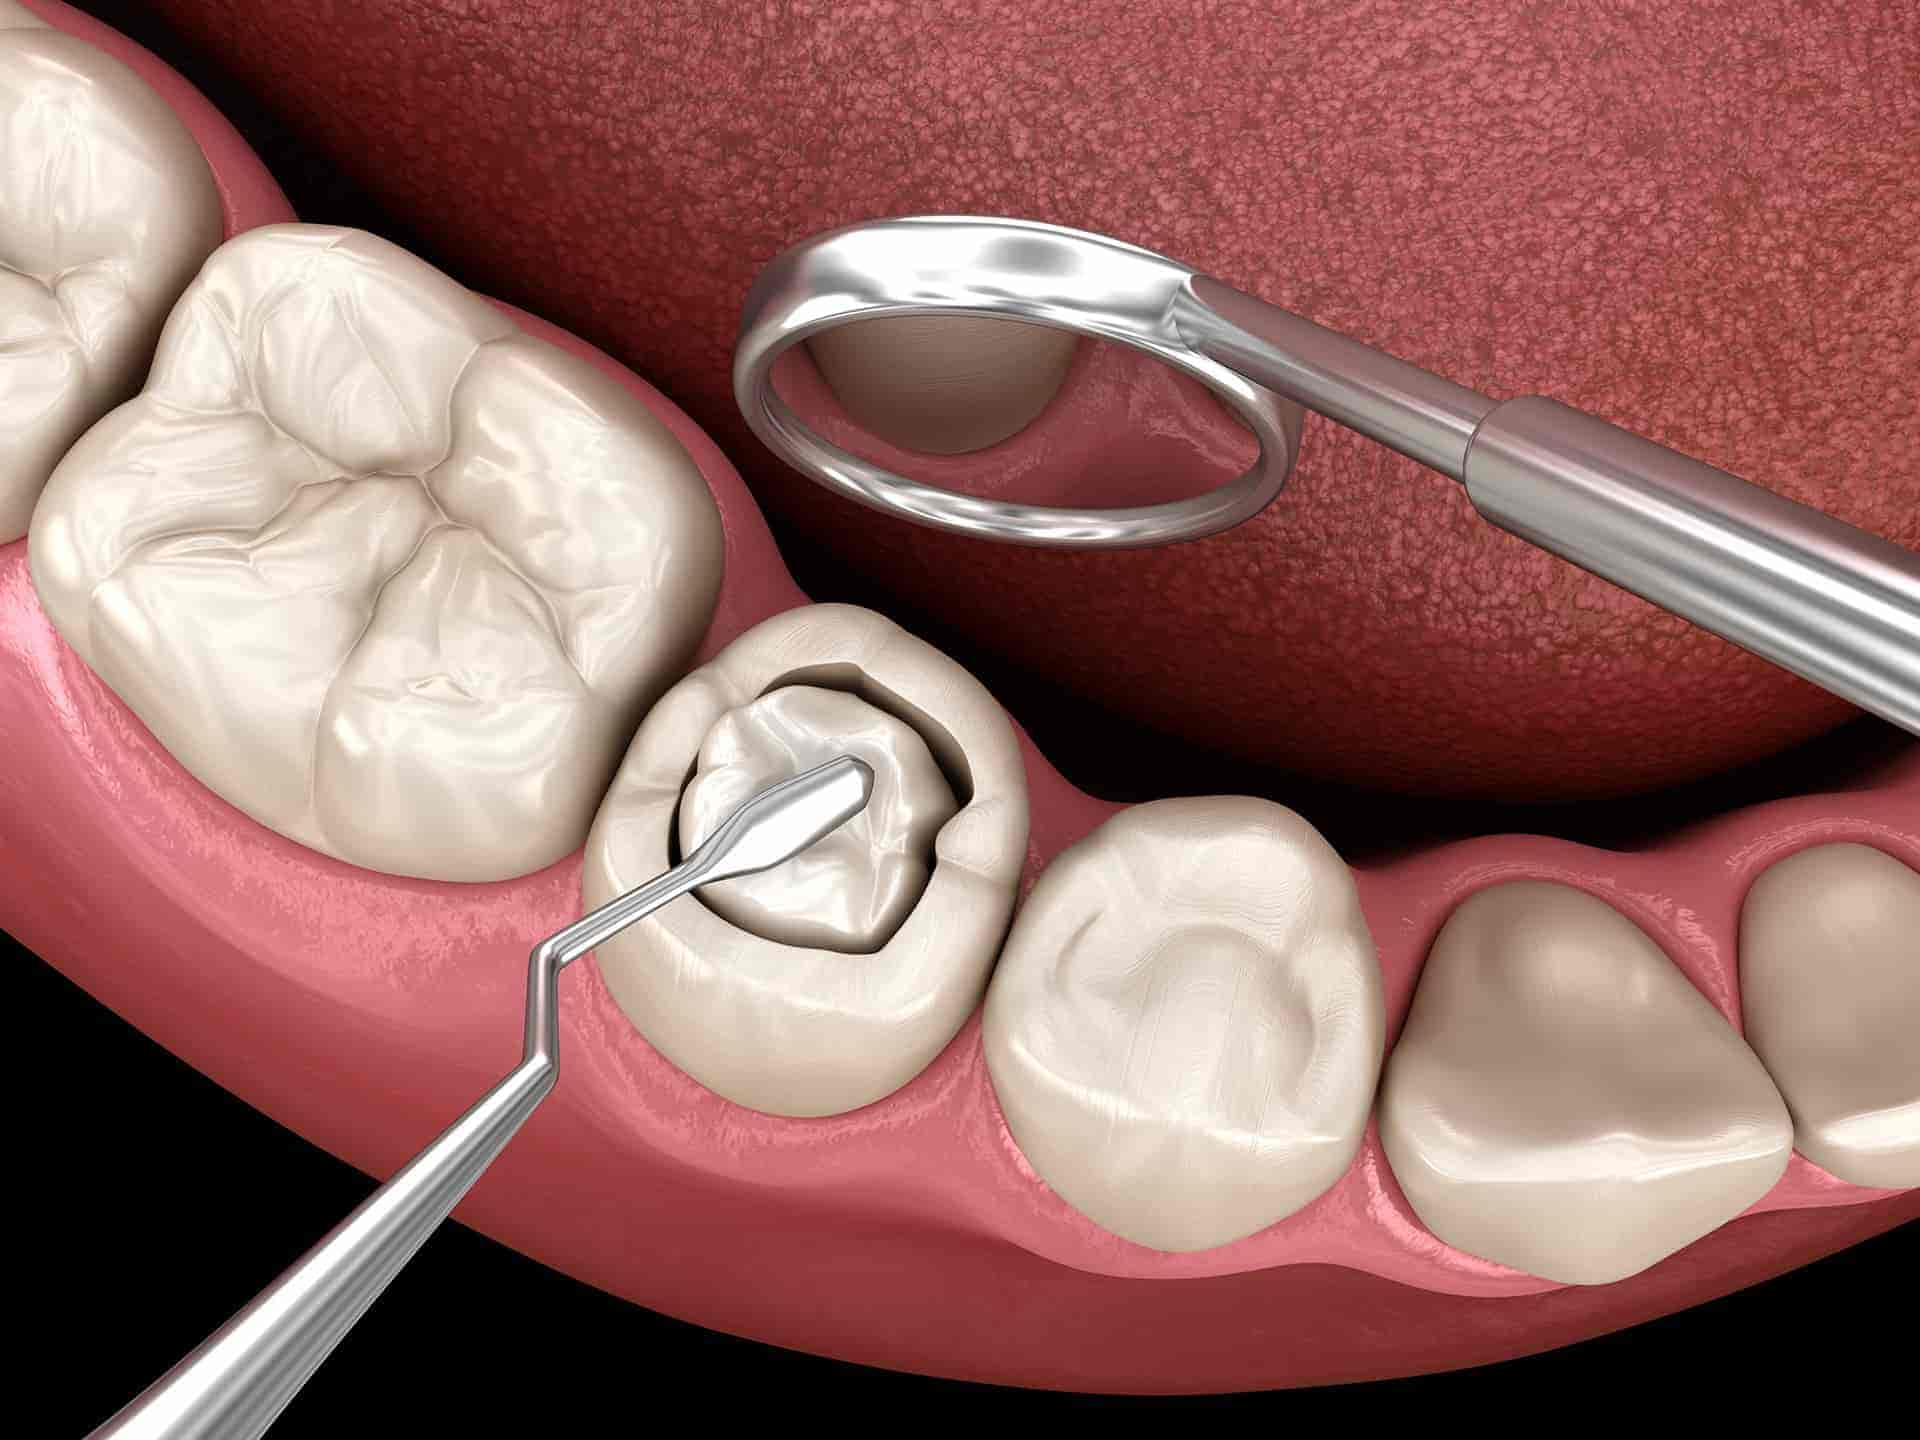

Restauracija zuba oštećenih karijesom. Nakon uklanjanja zaraženog tkiva, zub se nadoknađuje kompozitnim ili drugim savremenim materijalom, čime se obnavljaju funkcija, čvrstoća i estetski izgled zuba.